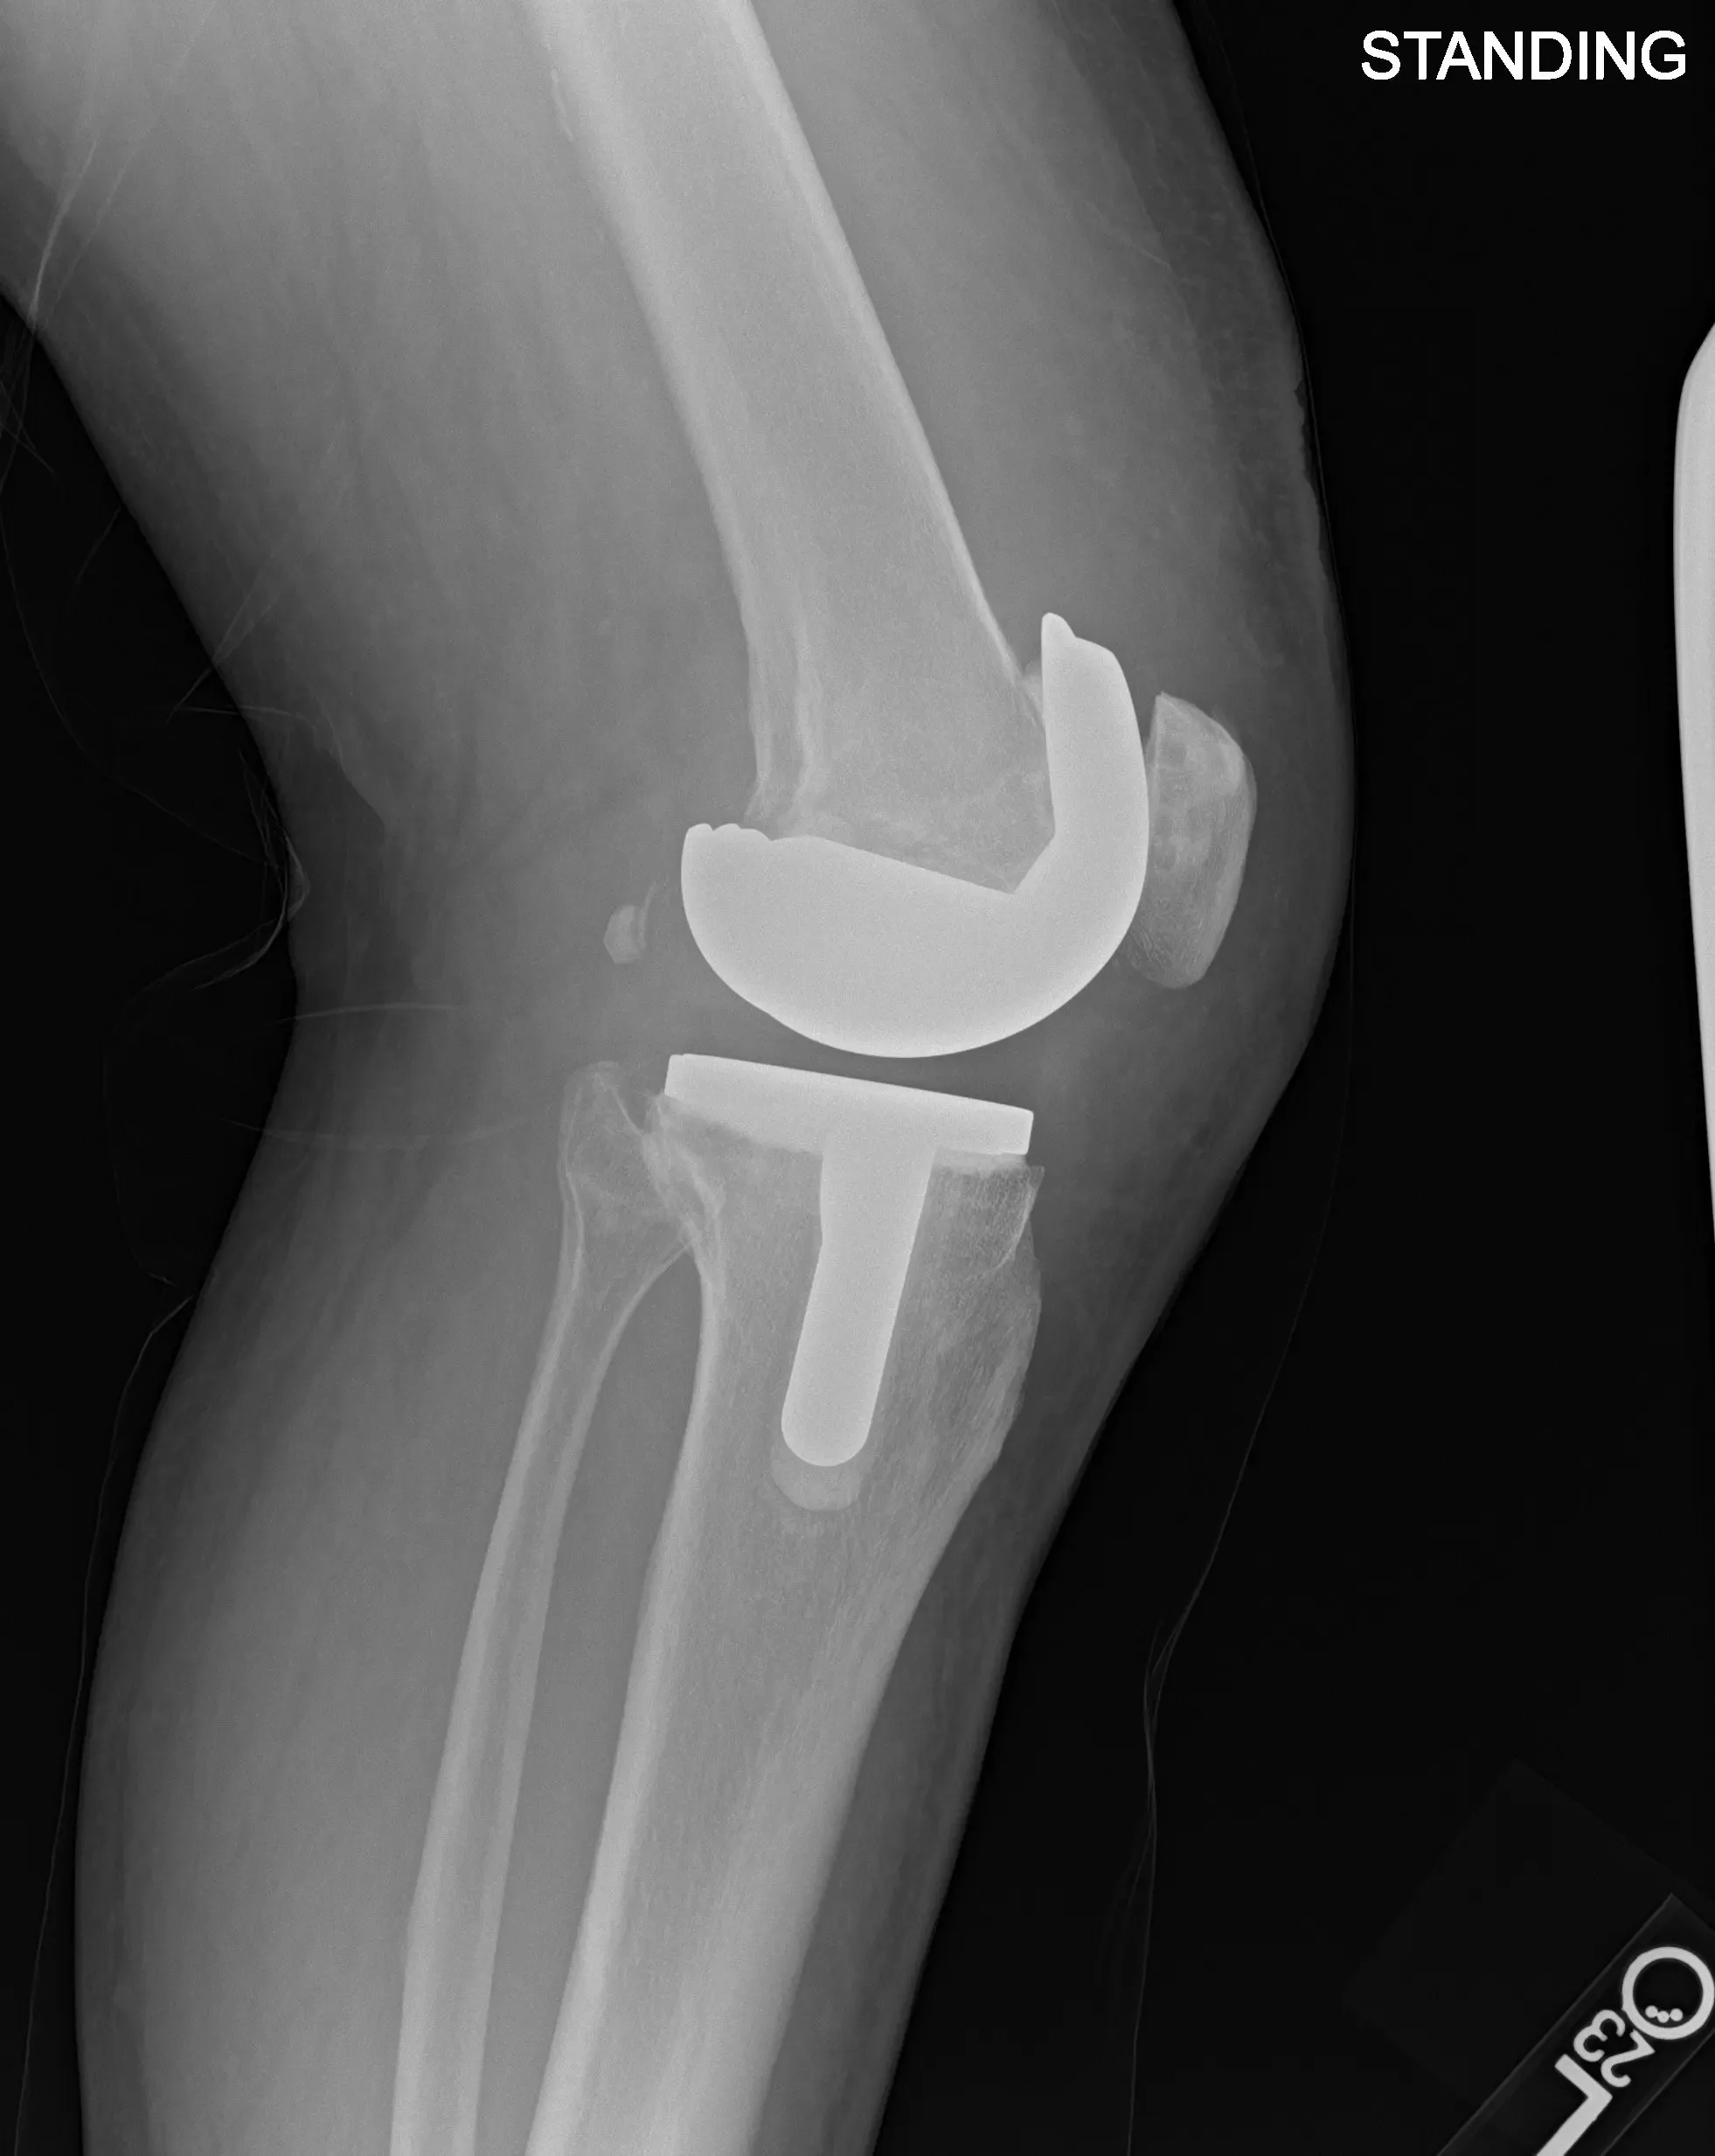

Postoperative X-ray images showing AP and lateral views of the left knee.

Implant used: Custom femoral implant with a custom tibial tray, with 8-mm polyethylene insert, with custom 32-mm x 6-m patellar implant.